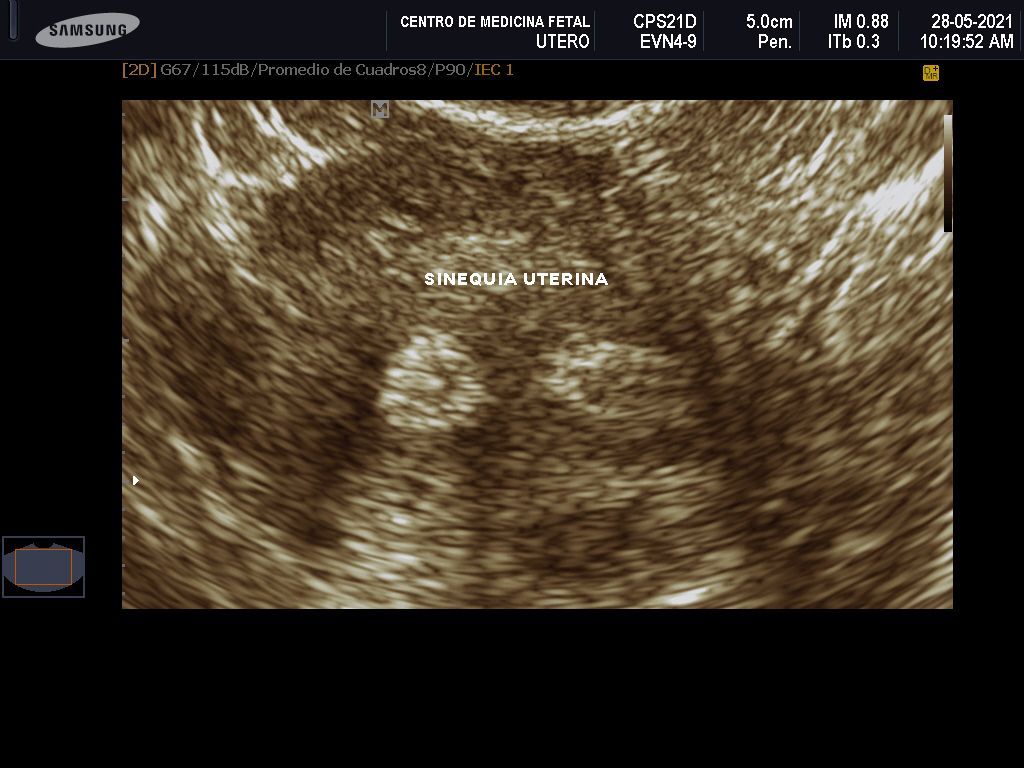

- Detección ecográfica transvaginal o pélvica y tratamiento de: Miomas, quistes de ovario, endometriosis, malformaciones uterinas